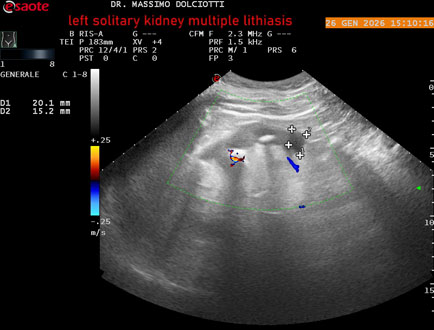

Data inserimento: 29/01/2026

Ecografia del: 26/01/2025

Strumento: Esaote MyLab Eight

Sonda: Conevx Multifrequenza 1-8 MHz

Età Paziente: M 78 anni

Motivazione dell'esame: follow up di litiasi al rene sinistro, in paziente sottoposto a nefrectomia destra.

Commento all'esame: le immagini ed il video documentano il rene sinistro in sede, di ecostruttura disomogenea per evidenza di multiple formazioni litiasiche al pielone superiore, delle dimensioni di 15,9 mm, al pielone medio di 17,5 mm e al pielone inferiore di 18,9 mm e morfovolumetria normale, con diametro bipolare di 115 (v.n. 90-120 mm) x 54 mm e parenchima renale dello spessore di 17 mm ( v.n. > 13 mm).

Conclusioni: litiasi multipla del monorene sinistro (multiple lithiasis of the left solitary kidney).

In collaborazione: Dr.ssa Marica Manfredi - Ancona, Dr. Ilir Qose - Ancona

Presentazione: Dr. Massimo Dolciotti - Ancona

Elaborazione digitale: Andrea Dini - Ancona